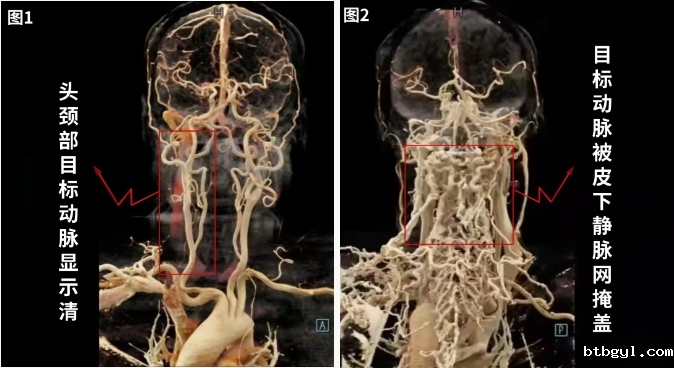

在日常进行静脉注射时,一般都会选择相对方便进针的静脉进行穿刺,与日常静脉注射不同的是,在进行CT检查时,放射科医护人员都会建议将留置针打在右上肢。这是为什么?。 首先正常情况下,大多数人是右利手,右上肢的活动相对频繁,这使得右上肢的血管通常较为明显。且容易定位,护士在进行穿刺时能够更准确地找到合适的血管。提高穿刺的成功率,减少反复穿刺给患者带来的痛苦。 其次,右上肢的锁骨下静脉直接汇入上腔静脉,路线较左侧短而通畅,而左侧锁骨下静脉需跨过主动脉弓之后才可以汇入上腔静脉,路程比较远而且比较崎岖。 在高速注射对比剂的情况下,容易由于压力太大导致对比剂冲入浅表的静脉网中,导致浅表静脉对比剂残留现象的发生。通俗地说:就是右上肢静脉离心脏更近,能够快速将对比剂送达心脏,随后经心脏进入动脉,随着血液循环到达需要检查的部位,而左上肢静脉则反之。 我们通过对比下面两组头颈部血管成像可以更加直观看出区别: 图1为通过右上肢注射的患者头颈CTA的图像,头颈部动脉显示清晰,方便我们快速准确的发现病变。图2左上肢注射的患者头颈CTA的图像,大量的对比剂还残存在皮下静脉中,这就导致了头颈部动脉被皮下静脉网掩盖,容易遗漏病灶,从而容影响诊断质量。 同时《影像增强检查静脉输注工具规范应用专家共识》中也有明确规定:如果患者行CT血管成像(CTA)检查,尤其是头颈动脉、冠状动脉、肺动脉CTA检查时,应尽量选择右侧上肢穿刺,可减少静脉伪影对图像质量造成影响。 因此在做CT增强和血管造影检查时,道路越通畅,检查的图像效果就会越好,更有利于影像的准确诊断,同时尽量减少不良反应的发生。我们建议:CT增强检查在预留静脉留置针时,能选在右侧就不选左侧(若病变刚好位于右侧颈部或右侧肺尖部位,可选择健侧左上肢);能选在上肢就不选下肢。